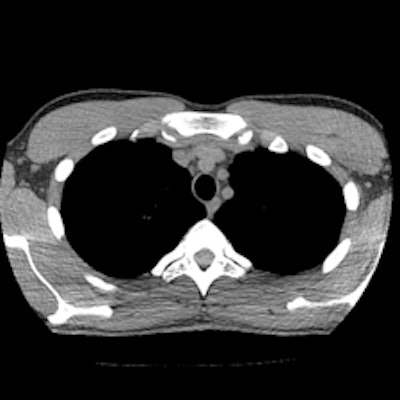

Chest CT images with reconstructions using different kernels; slices at the same position at the mediastinal level (Aquilion One, Toshiba Medical Systems). Left: Initial chest CT, reconstructed with the standard kernel (FC14). Right: Follow-up CT, reconstructed with a new, dedicated, dose-saving kernel (FC14). It becomes obvious that diagnostic image quality is maintained, despite more noise and artifacts using the new "dose-saving" kernel (right). All images courtesy of Dr. Erich Sorantin.But if the exam is merited, it should be performed with a 64-detector-row and higher CT system, or a volume CT scanner that has active collimation and faster scanning speeds to minimize the risk of overbeaming and overranging. Lead author Dr. Erich Sorantin, a pediatric radiologist and a professor at the Medical University of Graz in Austria, and colleagues recommend that radiographers consider all elements of a CT exam in which dose reduction might be possible, and to begin with the scout view (EJR, 8 January 2012, article in press).